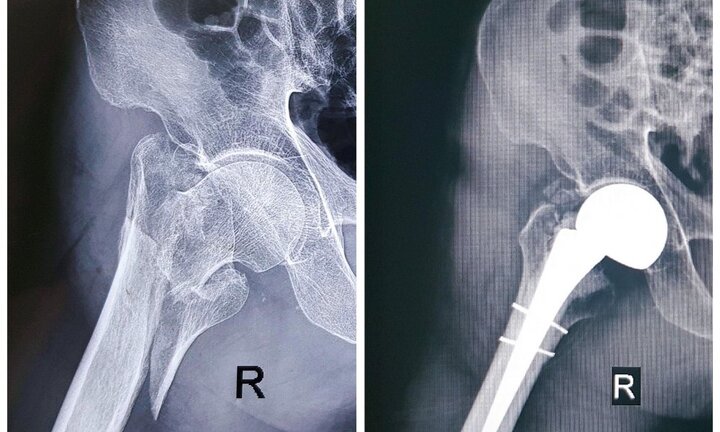

Bệnh viện Đa khoa Hà Đông (Hà Nội) vừa phẫu thuật thay khớp háng cho một cụ ông 96 tuổi, bị gãy liên mấu chuyển xương đùi phải.